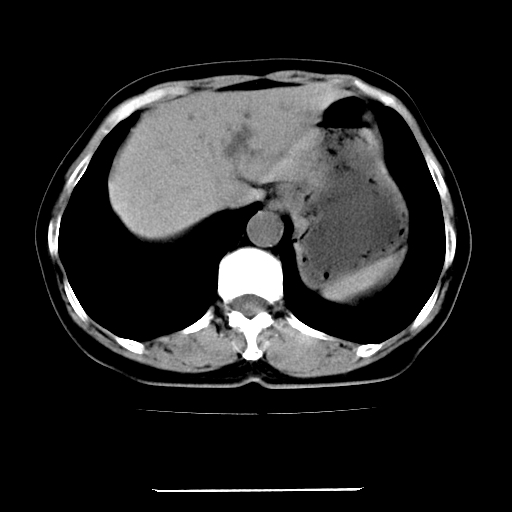

标题: CT22301:女,67岁,上腹部疼痛一周伴皮肤黄染,无发热。 [打印本页]

女,67岁,上腹部疼痛一周伴皮肤黄染,无发热。

左叶肝内胆管结石,并远端肝内胆管扩张。

考虑:肝内胆管结石继发肝内胆管扩张,右肾旋转不良。

肝内外胆管结石并肝内胆管扩张。

建议薄层观察,除外肝门部胆管细胞癌

考虑肝胆管癌;胰头占位?【形态失常,体积增大】

1、肝门高密度影下层面和胰头层面可见轻度胆管扩张,而静脉和延迟期均未见扫描完胰头,不能完全排除胰头占位。2、肝门部高密度影,考虑钙化或结石。

考虑肝门胆管癌伴门脉左支受侵包埋,建议mrcp进一步检查。